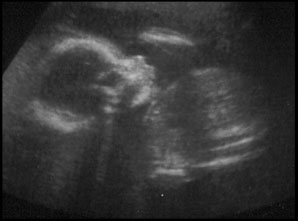

And now for the pictures. I'm only putting up two... they're the best of the lot we got.

Here is her profile. To the left is her head, nose, lips, and her right hand is up by her cheek. Then to the right is her torso.